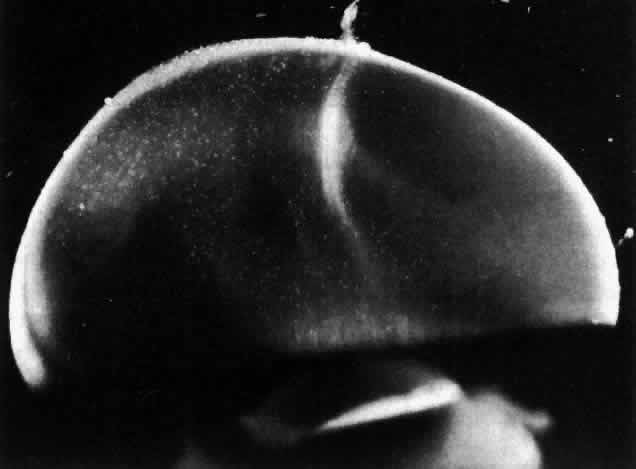

Dissection of the outer layers of the eye (sclera, choroid, and retina) can be performed and the “naked” vitreous body can be maintained intact and attached to the anterior segment of the eye (Fig. 2). This enables study of internal vitreous morphology without a loss of intraocular orientation. However, depending on the age of the subject and consequently the degree of vitreous liquefaction,87 the dissected vitreous will remain solid and intact (young individuals, see Fig. 2) or will be flaccid and collapse. The latter is most often the case in specimens from older adults, and consequently vitreous turgescence must be maintained so as to avoid distortion of intravitreal morphology. Immersion of a dissected vitreous specimen that is still attached to the anterior segment into a physiologic solution maintains vitreous turgescence and avoids structural distortion.

Fig. 2. Human vitreous dissection. A. Vitreous obtained at autopsy from a 9-month-old child. The sclera, choroid, and retina were dissected off the vitreous, which remains attached to the anterior segment. A band of gray tissue can be seen posterior to the ora serrata. This is neural retina that was firmly adherent to the vitreous base and could not be dissected. Because of the young age of the donor, the corpus vitreous is almost entirely gel. Thus, it is solid and maintains its shape, although situated on a surgical towel exposed to room air. (Sebag J: The Vitreous--Structure, Function and Pathobiology. New York, Springer-Verlag, 1989) B. Human vitreous with the sclera, choroid, and retina dissected away; the corpus vitreous is still attached to the anterior segment. The specimen is mounted on a Lucite frame using sutures through the limbus and then immersed in a Lucite chamber containing an isotonic, physiologic solution. This maintains vitreous turgescence and avoids collapse and artifactual distortion of vitreous structure. (Sebag J, Balazs EA: Pathogenesis of cystoid macular edema: An anatomic consideration of vitreoretinal adhesions. Survey Ophthalmol 28[suppl]:493, 1984)